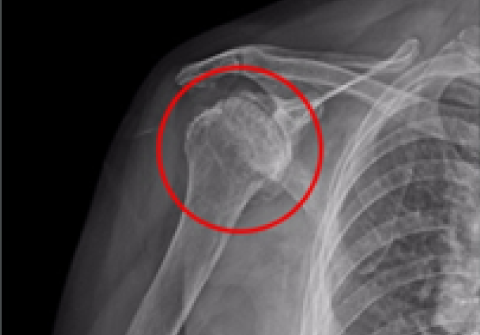

노화된 어깨의 관절낭을 절제해 간격을 넓혀주는 수술방법

2015.10.05

2016.02.22

어깨 인공관절 역 전치환술

2013.10.05

2013.12.19

어깨 인공관절 부분치환술

2010.11.23

2011.03.17